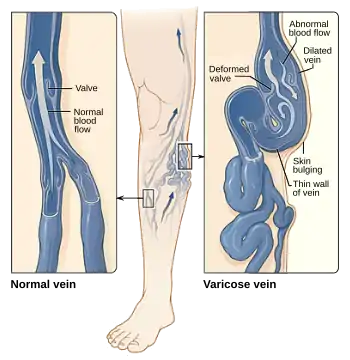

Multiple arteriovenous fistulas: PWS patients also have multiple AVFs that occur in conjunction with capillary malformations. AVFs occur because of abnormal connections between arteries and veins.[5] Normally, blood flows from arteries to capillaries then to veins. But for AVF patients, because of the abnormal artery and vein connections, blood flows directly from arteries into the veins completely bypassing the capillaries.[9] These irregular connections affect the blood circulation and may lead to life-threatening complications such as abnormal bleeding and heart failure. AVFs can be identified by: large, purplish bulging veins, swelling in limbs, decreased in blood pressure, fatigue and heart failure.[9]

The Human Phenotype Ontology (HPO) reports of additional symptoms in PWS patients. HPO is an active database that collects and researches on the relationships between phenotypic abnormalities and biochemical networks.[11] This is a useful database as it has information and data on some of the rarest diseases such as PWS. According to HPO, the symptoms which are reported very frequently in PWS patients include: abnormal bleeding, hypertrophy of the lower limb, hypertrophy of the upper limb, nevus flammeus or staining of the skin, peripheral arteriovenous fistula, telangiectasia of the skin. Frequent to occasional symptoms include: varicose veins, congestive heart failure, glaucoma and headache.

Varicose veins: Enlarged, swollen and twisted veins.[11]